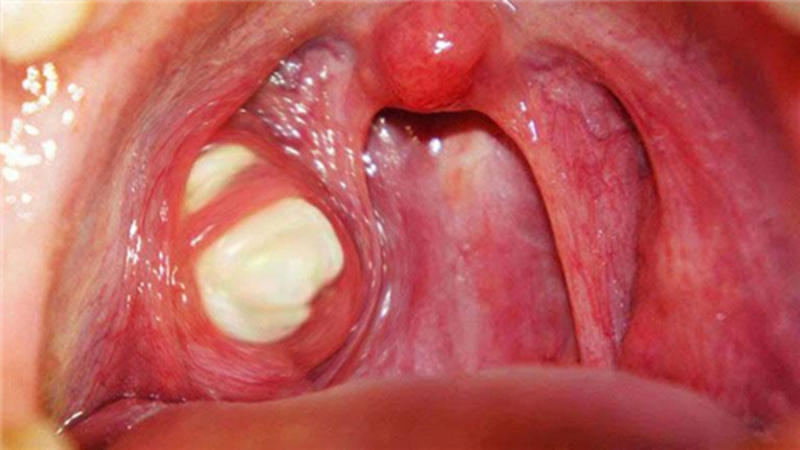

Viêm amidan có mủ là sự xuất hiện những khối mủ màu trắng bã đậu, đóng kết vón cục trên rãnh hốc ở trên các bề mặt amidan, chúng thường có mùi hôi.

Đây là loại tổn thương viêm do viêm nhiễm cấp hoặc viêm mạn tính amidan do ảnh hưởng của vi khuẩn hoặc virus, nếu để bệnh tiến triển nặng sẽ gây nguy hiểm đến người bệnh. Bệnh có thể xuất hiện ở bất kỳ đối tượng nào, khi bị viêm amidan mủ người bệnh sẽ bị khó chịu hay bị đau đớn và lâu dần cũng có thể gây ung thư nên cần được kịp thời chữa trị.